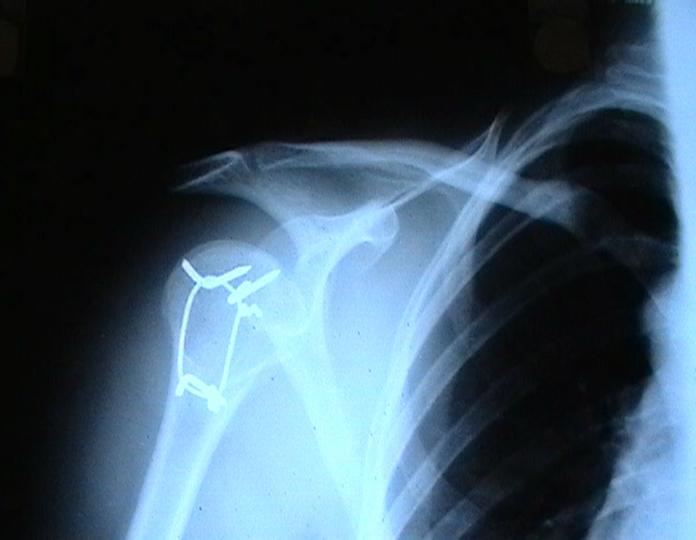

Переломовывих плеча сложная проблема и технически не уверен как для коллег, но для меня сколько я не встречался, технически сложно *вытянуть* вывихнутую головку из-под впадины. Последнее время не применяю пластины для фиксации перелома, а использую спицы и проволочную петлю (тем более часто и густо спонгиозные винты не держатся в головке прочно).

Момент , который следует учитывать при использовании такого рода фиксации - необходимо быть уверенным , что спицы не проникают в сустав, поэтому полезно пользоваться ЭОпом для контроля или интраоперационными рентгенограммами

перед ушиванием раны.

Фиксация получается достаточно стабильная, правда мои заключения основаны только на клинических наблюдениях, возможности протестировать прочность фиксации в лабораторных условиях нет. Я не автор данного типа фиксации в основе его лежит принцип напряженной фиксации (Weber tension Band fixation). Когда-то у нас использовали фиксатор проф Сеппо при переломах

шейки бедра - принцип работы аналогичен, только менее громоздкие элементы конструкции и более доступные для применения в любых условиях.

Не происходит ли миграция спиц?

Я использую обычные 2 мм спицы и пока в 8 случаях , что применял подобную фиксацию миграции не было, хотя вполне вероятна такая возможность и видимо оптимальнее использовать спицы с резьбой на конце, что должно предотвратить потенциальный риск миграции. Хотя если спица начинает пальпироваться под кожей и доставлять неудобство больному, то её легко удалить в условиях перевязочной. На мой взгляд миграция спицы мложет произойти только тогда,

когда пациент начинает активно работать рукой, к этому времени перелом уже срастется, поэтому опасности скомпрометировать стабильность фиксации уже не будет.

Я такой же практик как и Вы, поэтому решать можно или нельзя использовать только проволочную петлю решать Вам, хотя на мой взгляд, обычная проволочная петля не создает многоплоскостной стабильности фиксации, а только лишь в плоскости проведенных отверстий в проксимальном и дистальном фрагментах и другой момент зачастую такие переломы случаются у пожилых людей с порозной костью, тогда, как понимаете, проволочная петля может легко прорезаться через кость и не о какой стабильной фиксации уже речи быть не может в то время как спицы держаться в порозной кости тем более, что при такой фиксации создается момент силы, направленный не на вытягивание спицы из кости.